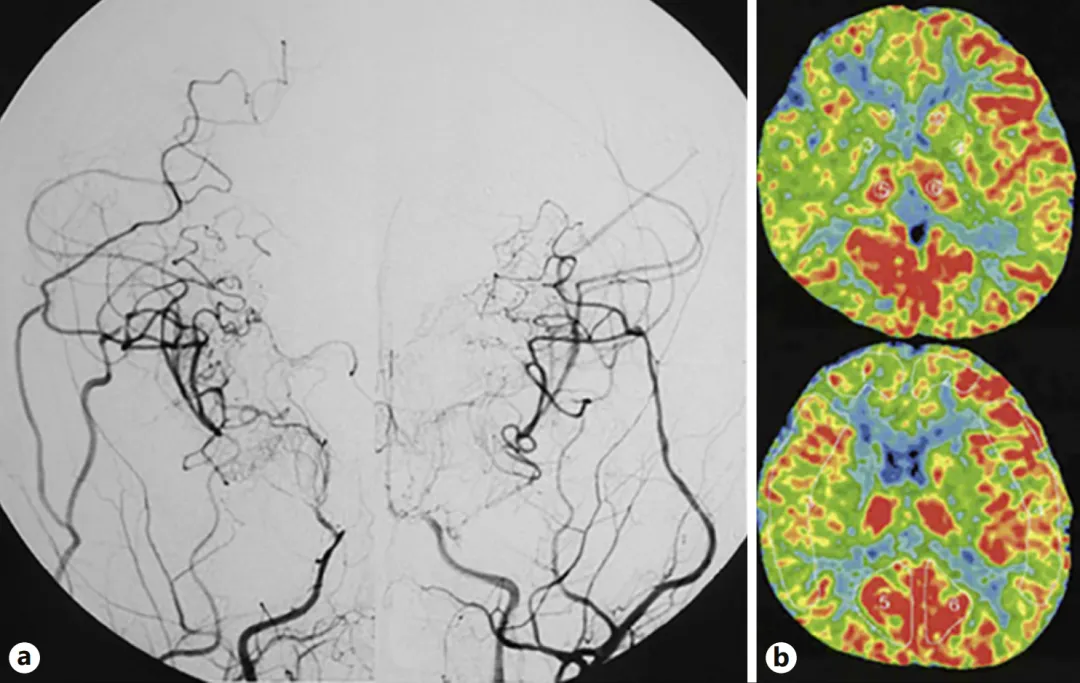

图a:二次术后半年,双侧颈内动脉血管造影显示侧支血管网络发育良好,基底烟雾血管消退。

图b:双侧脑血流显示改善征象。

术后患儿恢复良好,复查DSA显示侧支循环建立良好,基底节区烟雾血管减少,脑血流显著改善。但术后仍需继续用药预防血栓形成并严格控制血压水平。